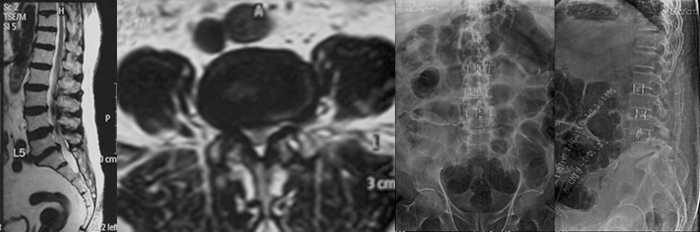

The nerve roots that connect the lower part of the trunk and the lower limbs to the spinal cord and brain lie in the lumbar spinal canal. These nerves are responsible for power and sensation of the legs and the buttocks and genitalia along with the control of bladder, bowel and sexual functions.

Lumbar radiculopathy is often caused by a prolapsed disc causing low back pain with radiation to the leg/s. Pain may be associated with tingling, numbness, pins and needles like sensation and weakness of the leg/s. In most cases, the symptoms ease off gradually over several weeks with analgesics, good physiotherapy and normal activities. Surgery is an important option if the symptoms persist or progress.

FAQs:

- How many days do I need to stay in Hopsital?

Patients are usually admitted to the hospital a day before surgery. After operation patients will be up and walking within the first day. If surgery is being done for leg pain due to nerve root compression, the pain improves significantly immediately following operation. Weakness or numbness, however, may take longer to improve. Patients are usually discharged on the 3rd day, allowing us to make sure that pain is well-controlled on oral medications and that the patient can move around indoors freely and without support prior to going home. - How long does this surgery take?

The time taken for operation depends on each individual patient’s physical structure (e.g. height and weight) and diagnosis. The actual time needed for operation also depends on the number of levels to be decompressed and fused. - Are there risks involved in this surgery?

There are risks and benefits of every medical and surgical intervention. Complications are rare, and, if they occur, usually mild. The risks of surgery include foot weakness, foot drop, persistent pain after surgery, spinal nerve damage and tear of the sac around the nerves and problems in passing/holding urine and stool. There is also a risk that the level above or below the operated level will have an accelerated rate of degeneration. Infection and malposition or loosening of the screws are occasionally encountered. Around 10% of patients will have some temporary complications most of which are treatable and improve with time. Only 1% of patients may have some permanent deficits most of which will be of a trivial or minor nature. The risks of anaesthesia are largely dependent on the patient’s general physical health which will be investigated by the anaesthesiology team prior to surgery. The treating surgeon and anaesthesiologist will discuss these risks in the fullest detail during the pre-operative visit. - What is the follow up protocol?